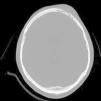

El Pott's puffy tumor (PPT) es una rara entidad que en la actualidad representa un abombamiento del cuero cabelludo asociado a un absceso subperióstico y a una osteomielitis craneal, pudiendo acompañarse o no de infección intracraneal. Suele asociarse a la sinusitis frontal, tratándose de una complicación típica, aunque poco frecuente de la misma. Por su parte las osteomielitis causadas por Actinomyces son raras y suelen tener lugar a nivel mandibular, no encontrándose apenas casos de osteomielitis craneal causada por este género bacteriano, en especial tras traumatismo craneoencefálico. Presentamos un caso especialmente poco usual al tratarse de un PPT frontal tras traumatismo cerrado, con componente intracraneal y en el que tras cirugía se aisló Actinomyces como copartícipe de dicha infección, junto con Fusobacterium y Propionibacterium.

Pott's puffy tumour (PPT) is a rare entity that involves scalp swelling associated with subperiosteal abscess and cranial osteomyelitis, occasionally accompanied by intracranial infection. It is usually affiliated with frontal sinusitis, which is a typical but infrequent complication. On the contrary, Osteomyelitis by Actinomyces is rare and usually occurs at the mandibular level, with very few cases of cranial osteomyelitis caused by this bacterial specie, especially after traumatic brain injury. We report an exceptionally unusual case of a PPT frontal tumor after blunt trauma (closed head injury), with an intracranial lesion whereby Actinomyces was isolated after surgery, as a co-participant of the mentioned infection besides Fusobacterium and Propionibacterium.